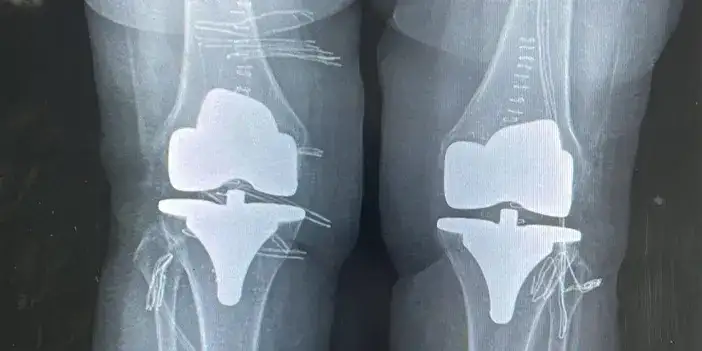

Bayburt' Devlet Hastanesinde çift taraflı diz protez ameliyatı!

Bayburt Devlet Hastanesinde yapılan çift taraflı total diz protezi operasyonuyla 73 yaşındaki hastanın dizlerindeki ağrı giderildi. Başarılı geçen ameliyatla hasta sağlığına kavuştu.

Ortopedi polikliniğine dizlerindeki yoğun ağrı şikayetiyle başvuran 73 yaşındaki hastanın her iki dizinde ileri derecede kireçlenme tespit edildi. Ortopedi ve Travmatoloji Uzmanı Op. Dr. Reşat Arıkan tarafından gerçekleştirilen operasyonda, hastanın her iki dizine çift taraflı total diz protezi uygulandı. Tek seferde yapılan ve başarılı geçen bilateral ameliyatının ardından hastanın sağlık durumunun iyi olduğu öğrenildi.